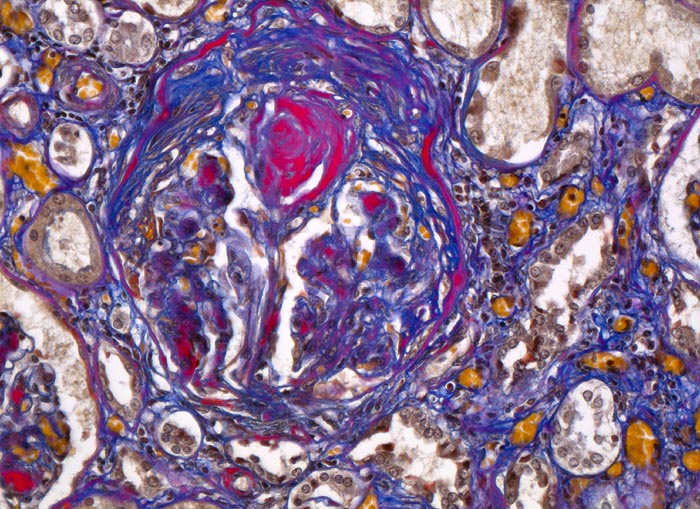

Im allgemeinen ist die Niere infolge von Glomerulumhypertrophie und Tubulushyperplasie vergrössert und derb, die Oberfläche ist granuliert. Bei schwerer Atherosklerose und fortgeschrittener Niereninsuffizienz kann die Niere auch normal gross oder verkleinert sein. Die Kombination von nodulärer Glomerulosklerose, hyalinen Schlingenkappen (=Proteinthromben in den Glomerulumschlingen (> 1916)) oder Kapseltropfen (> 1907) und Arteriolosklerose in Vas afferens und efferens ist beweisend für eine diabetische Nephropathie. Jede einzelne Läsion für sich genommen ist aber unspezifisch. Eine noduläre Glomerulosklerose kann auch vorkommen bei membranoproliferativer Glomerulonephritis (> 2652), Leichtkettenglomerulopathie oder Amyloidose (> 2019). Der nodulären Glomerulosklerose geht bei Diabetikern eine diffuse Glomerulosklerose (> 1906) voraus. Dabei zeigen die glomerulären Basalmembranen und das Mesangium eine progrediente gleichförmige Verbreiterung. Bei der nodulären und diffusen Glomerulosklerose handelt es sich aber wahrscheinlich um zwei pathogenetisch unterschiedliche, sich überlagernde Krankheitsbilder. Typisch bei Diabetikern ist im Unterschied zur arteriellen Hypertonie die Arteriolosklerose von Vas afferens und efferens (> 1911) und oft auch der Vasa recta. Intrarenale Arterien können eine Atherosklerose mit Atheromen zeigen. Subendotheliale Proteinablagerungen teilweise mit Verschluss der Glomerulumschlingen (Schlingenkappen) und knotige Proteinablagerungen in der Bowman'schen Kapselbasalmebran (Kapseltropfen) gehören zu den sogenannten exsudativen Läsionen (> 1919) (> 1920) der diabetischen Nephropathie und führen zu Synechien sowie zur globalen Glomerulosklerose. Gleichzeitig mit den Glomerulumveränderungen treten tubuläre Basalmembranverbreiterungen auf, später eine Tubulusatrophie und interstitielle Fibrose mit Begleitentzündung. Auch die Basalmembranen der peritubulären Kapillaren sind verdickt.

• Verbreiterung des Mesangiums mit Ausbildung von Knoten(noduläre Glomerulosklerose).

• Exsudative Läsionen: Hyaline Schlingenkappen (Proteinthromben in Glomerulumschlingen, im virtuellen Präparat nicht sichtbar) und Kapseltropfen (Proteinablagerungen im Bowman’schen Kapselraum).

• Arteriolosklerose von Vas afferens und efferens (Gefässwandhyalinose durch Ablagerung von Plasmaproteinen und Lipiden in der Gefässwand).